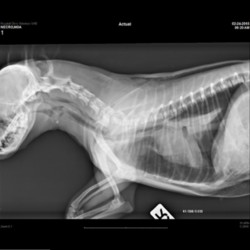

Pàgina anterior de 637 Pàgina següent 3181 total Porcine Specie: Porcine Organ: Lung Lesion: Pneumonia Lesion modifier: Pneumonia - Interstitial - Subacute Disease: Porcine reproductive and respiratory syndrome Files/Expedient: N-65/15 Position: 253 (1 views) Porcine Specie: Porcine Organ: Lung Lesion: Pneumonia Lesion modifier: Pneumonia - Interstitial - Subacute Disease: Porcine circovirosis Files/Expedient: N-65/15 Not viewed Avian (Poultry) Specie: Avian (Poultry) Organ: Oviduct Lesion: Salpingitis Lesion modifier: - Disease: - Files/Expedient: N-61/15 Not viewed Avian (Poultry) Specie: Avian (Poultry) Organ: Oviduct Lesion: Salpingitis Lesion modifier: - Disease: - Files/Expedient: N-61/15 Not viewed Canine Specie: Canine Organ: Thoracic cavity Lesion: Atelectasis Lesion modifier: - Disease: - Files/Expedient: N-60/15 Not viewed Pàgina anterior de 637 Pàgina següent Títol Select...Avian (Exotic) (110)Avian (Poultry) (76)Bovine (317)Canine (935)Caprine (47)Equine (257)Feline (326)Ferret (19)General (127)Marine mammal (22)Non-human primate (20)Ovine (328)Porcine (379)Rabbit (61)Reptile (38)Rodent (28)Wildlife (91) Format Select...- (60)Abomasum (37)Adrenal gland (10)Blood (7)Blood vessel (50)Body as a whole (19)Bone (57)Bone marrow (21)Brain (93)Cloaca (1)Diaphragm (2)Ear (5)Esophagus (39)Eye (16)Fetus (12)Gallbladder (23)Gizzard (2)Heart (265)Intestine (356)Joint (32)Kidney (443)Larynx (5)Liver (326)Lung (264)Lymph node (91)Mammary gland (10)Mediastinum (1)Muscle (22)Nasal cavity (22)Nerve (7)Omasum (5)Oral cavity (63)Ovary (14)Oviduct (8)Pancreas (7)Parathyroid (5)Penis (10)Peritoneum (65)Pharynx (9)Pituitary gland (6)Placenta (7)Prostate (8)Proventriculus (3)Reticulum (1)Rumen (28)Sinus (7)Skin (181)Spinal cord (15)Spleen (105)Stomach (125)Teeth (1)Testicle (11)Thoracic cavity (31)Thymus (13)Thyroid gland (5)Tongue (32)Tonsils (11)Trachea (11)Urethra (5)Urinay bladder (61)Uterus (27)Vagina (1)Vulva (1)Yolk sac (1) Cobertura Select...- (152)Abomasitis (26)Abscess (27)Acidosis (1)Adenocarcinoma (20)Adenoma (9)Aerosacculitis (6)Agenesis (1)Agnathia (1)Alopecia (7)Amyloidosis (12)Aneurysm (6)Angiectasis (1)Anthracosis (1)Arteritis (11)Arthritis (15)Arthrogryposis (6)Artifact (4)Ascites (13)Atelectasis (8)Atherosclerosis (5)Atresia (1)Atrial septal defect (2)Atrophy (10)Autolysis (7)Bronchitis (6)Bronchopneumonia (26)Cachexia (2)Carcinoma (103)Cardiomyopathy (19)Cellulitis (2)Chemodectoma (4)Cholangiohepatitis (4)Cholangitis (19)Cholecystitis (4)Cholestasis (5)Chondrodysplasia (2)Chondrosarcoma (2)Chronic passive congestion (13)Chylothorax (2)Cirrhosis (6)Coelomitis (3)Coenurus cerebralis (4)Colitis (40)Congestion (17)Conjunctivitis (5)Coronitis (3)Cryptorchidism (3)Cyst (25)Cystitis (24)Dermatitis (69)Diaphragmatic hernia (4)Dilation (28)Discospondylitis (1)Disseminated intravascular coagulation (7)Dyschondroplasia (1)Dysplasia (29)Ectopia cordis (1)Ectopic ureter (1)Edema (55)Emphysema (5)Encephalitis (5)Endocardiosis (14)Endocarditis (26)Endometritis (5)Enteritis (118)Enterolith (6)Epulis (3)Esophagitis (14)Fasciitis (1)Fibrosis (7)Fibrous osteodystrophy (8)Fistula (1)Folliculitis (3)Fracture (2)Gastritis (34)Gingivitis (5)Glioma (8)Glomerulonephritis (21)Glossitis (25)Glycogenosis (1)Gout (8)Granuloma (2)Granulosa cell tumor (4)Hemangioma (9)Hemangiosarcoma (46)Hematoma (8)Hemoglobinuria (2)Hemopericardium (12)Hemoperitoneum (2)Hemorrhage (100)Hemosiderosis (7)Hemothorax (2)Hepatitis (78)Hernia (11)Histiocytosis (3)Hydatid cyst (11)Hydrocephalus (9)Hydrometra (1)Hydronephrosis (22)Hydropericardium (6)Hydrothorax (3)Hydroureter (5)Hyperkeratosis (8)Hyperostosis (4)Hyperplasia (37)Hypertrophy (9)Hypopigmentation (1)Hypoplasia (7)Hypopyon (1)Impaction (6)Infarction (63)Insulinoma (6)Intussusception (5)Jaundice (17)Laminitis (2)Laryngitis (2)Leiomyoma (5)Leukemia (13)Lipidosis (36)Lipoma (7)Lymphadenitis (45)Lymphadenopathy (7)Lymphangiectasia (6)Lymphangitis (5)Lymphoma (221)Malacia (11)Malignant melanoma (15)Mast cell tumor (11)Mastitis (8)Megaesophagus (2)Melanosis (3)Melena (4)Meningioma (6)Meningitis (6)Meningocele (2)Meningoencephalitis (5)Mesothelioma (5)Methemoglobinemia (2)Mineralization (10)Mucocele (5)Mucometra (1)Multilobular bone tumor (1)Mummification (3)Myelofibrosis (1)Myocarditis (4)Myositis (5)Necrosis (81)Nephritis (113)Nephroblastoma (6)Nephrosclerosis (1)Nephrosis (14)Neuritis (1)Obstruction (13)Omasitis (4)Omphalitis (1)Omphalophlebitis (7)Orchitis (4)Osteoarthrosis (5)Osteomyelitis (9)Otitis (2)Palatoschisis (3)Pancreatitis (3)Panniculitis (3)Papilloma (7)Parakeratosis (14)Patent ductus arteriosus (6)Peliosis hepatis (1)Perforation (17)Pericarditis (35)Peritonitis (39)Persistent right aortic arch (1)Pharyngitis (2)Pheochromocytoma (2)Phlebitis (2)Placentitis (6)Pleuritis (21)Pleuropneumonia (24)Pneumonia (109)Pneumothorax (3)Polycystosis (14)Polyp (5)Polyserositis (6)Posthitis (1)Proctitis (4)Prolapse (3)Prostatitis (3)Proventriculitis (1)Pyelonephritis (24)Pyometra (6)Pyothorax (4)Rhinitis (11)Rumenitis (6)Rupture (24)Salpingitis (3)Sarcoma (57)Sclerosis (1)Scoliosis (2)Seminoma (2)Sequestrum (2)Serous atrophy (14)Sinusitis (7)Splenitis (14)Splenomegaly (9)Spondylitis (6)Spondylosis (1)Stenosis (9)Stomatitis (32)Tenosynovitis (2)Teratoma (3)Thricobezoar (2)Thrombosis (16)Tonsilitis (4)Torsion (13)Tracheitis (4)Tympany (7)Typhlitis (8)Typhlocolitis (4)Ulcer (43)Urethritis (1)Urolithiasis (36)Uroperitoneum (1)Uveitis (1)Vasculitis (15)Ventricular septal defect (3)Volvulus (11) Matèria Select... - (14)- (1653)- (152)Abomasitis - Catarrhal (2)Abomasitis - Catarrhal-hemorrhagic (1)Abomasitis - Chronic (1)Abomasitis - Fibrinous-necrotizing (2)Abomasitis - Hyperplasic (5)Abomasitis - Hyperplasic - Chronic (1)Abomasitis - Necrotic (1)Abomasitis - Necrotizing (2)Abomasitis - Ulcerative (5)Adenocarcinoma (9)Aerosacculitis - Granulomatous (1)Amyloidosis - Chronic (1)Arteritis - Necrotic (2)Arteritis - Necrotizing (1)Arthritis - Chronic (4)Arthritis - Fibrinous-purulent (3)Arthritis - Serous (4)Arthritis - Subacute (1)Ascites - Serous (1)Atrophy - Serous (1)Bronchitis - Catarrhal (3)Bronchitis - Suppurative (1)Bronchopneumonia - Catarrhal-purulent (17)Bronchopneumonia - Fibrinous (1)Bronchopneumonia - Granulomatous (1)Bronchopneumonia - Purulent (1)Bronchopneumonia - Suppurative (5)Carcinoma - Adenocarcinoma (33)Carcinoma - Adenocarcinoma - Hepatocellular (2)Carcinoma - Adenocarcinoma - Mucinous (1)Carcinoma - Basosquamous (1)Carcinoma - Cholangiocellular (3)Carcinoma - Hepatocellular (4)Carcinoma - Metastatic (3)Carcinoma - Squamous cell carcinoma (13)Carcinoma - Transitional cell (2)Cardiomyopathy - Dilated (13)Cardiomyopathy - Hypertrophic (6)Cellulitis - Necrotizing (1)Cholangitis - Chronic (8)Cholangitis - Hyperplasic (3)Cholecystitis - Fibrinous-necrotizing (1)Coelomitis - Fibrinous (1)Coelomitis - Granulomatous (1)Colitis - Catarrhal (3)Colitis - Catarrhal-hemorrhagic (1)Colitis - Fibrinous (1)Colitis - Fibrinous-necrotizing (1)Colitis - Fibrinous-necrotizing (Diphtheritic) (6)Colitis - Granulomatous (2)Colitis - Hemorrhagic (4)Colitis - Hemorrhagic-necrotizing (3)Colitis - Necrotizing (2)Colitis - Ulcerative (6)Congestion - Chronic (2)Conjunctivitis - Hyperplasic (1)Conjunctivitis - Purulent (3)Coronitis - Ulcerative (1)Cystitis - Chronic (3)Cystitis - Fibrinous (1)Cystitis - Fibrinous-necrotizing (1)Cystitis - Follicular (1)Cystitis - Hemorrhagic (6)Cystitis - Hemorrhagic-ulcerative (1)Cystitis - Necrotizing (9)Cystitis - Perforated (1)Dermatitis - Granulomatous (14)Dermatitis - Hyperkeratotic (10)Dermatitis - Hyperplasic (proliferative) (1)Dermatitis - Hyperplastic (10)Dermatitis - Necrotizing (4)Dermatitis - Pustular (4)Dermatitis - Ulcerative (2)Dilation - Chronic (1)Discospondylitis - Necrotizing (1)Dysplasia - Follicular (5)Edema - Interstitial (6)Emphysema - Interstitial (1)Encephalitis - Granulomatous (1)Encephalitis - Nonsuppurative (1)Endocardiosis - Mitral (7)Endocardiosis - Mitral - Chronic (5)Endocarditis - Valvular (6)Endocarditis - Valvular - Mitral (7)Endocarditis - Valvular - Pulmonic (1)Endocarditis - Valvular - Subacute (1)Endocarditis - Valvular - Subaortic (5)Endocarditis - Valvular - Tricuspid (4)Endometritis - Purulent (3)Endometritis - Purulent-hemorrhagic (2)Enteritis - Catarrhal (23)Enteritis - Catarrhal - Acute (1)Enteritis - Catarrhal-hemorrhagic (5)Enteritis - Catarrhal-hemorrhagic - Acute (2)Enteritis - Fibrinous (16)Enteritis - Fibrinous - Acute (3)Enteritis - Fibrinous-necrotizing (7)Enteritis - Granulomatous (14)Enteritis - Granulomatous - Chronic (1)Enteritis - Granulomatous - Multifocal (1)Enteritis - Hemorrhagic (17)Enteritis - Hemorrhagic - Acute (1)Enteritis - Hemorrhagic-necrotizing (1)Enteritis - Hyperplasic (proliferative) (4)Enteritis - Necrotizing (4)Enteritis - Necrotizing - Acute (1)Enteritis - Necrotizing - Hemorrhagic (1)Enteritis - Necrotizing-ulcerative (2)Enteritis - Ulcerative (1)Enteritis - Ulcerative-hemorrhagic (1)Esophagitis - Erosive-ulcerative (6)Esophagitis - Necrotizing (4)Esophagitis - Ulcerative (1)Esophagitis - Ulcerative-necrotizing (1)Fasciitis - Fibrinous-purulent (1)Folliculitis - Purulent (2)Gastritis - Catarrhal (2)Gastritis - Chronic (1)Gastritis - Follicular (1)Gastritis - Hemorrhagic (2)Gastritis - Hemorrhagic-necrotizing (1)Gastritis - Hypertrophic (2)Gastritis - Inclusion bodies (1)Gastritis - Mineralization (1)Gastritis - Mycotic (1)Gastritis - Necrotizing (2)Gastritis - Ulcerative (6)Gastritis - Uremic (3)Gingivitis - Erosive (2)Gingivitis - Hyperplasic (proliferative) (1)Gingivitis - Necrotizing (1)Glomerulonephritis - Chronic (7)Glomerulonephritis - Membranoproliferative (3)Glomerulonephritis - Membranoproliferative - Chronic (1)Glomerulonephritis - Membranous (3)Glomerulonephritis - Membranous - Chronic (1)Glomerulonephritis - Proliferative (2)Glomerulonephritis - Subacute (1)Glossitis - Erosive (2)Glossitis - Granulomatous (6)Glossitis - Hyperplasic (1)Glossitis - Hyperplasic (proliferative) (2)Glossitis - Hyperplastic (1)Glossitis - Necrotizing (2)Glossitis - Necrotizing - Focal (1)Glossitis - Ulcerative (6)Glossitis - Ulcerative - Multifocal (1)Glossitis - Ulcerative - Subacute (1)Glycogenosis (1)Granuloma - Eosinophilic (1)Hemangiosarcoma - Metastatic (2)Hemorrhage - Acute (1)Hemorrhage - Subcapsular (3)Hepatitis - Abscess (9)Hepatitis - Acute (3)Hepatitis - Chronic (4)Hepatitis - Chronic interstitial (6)Hepatitis - Granulomatous (7)Hepatitis - Interstitial - Multifocal (1)Hepatitis - Interstitial - Subacute (1)Hepatitis - Necrotizing (17)Hepatitis - Necrotizing - Acute (2)Hepatitis - Necrotizing - Hemorrhagic (1)Hepatitis - Necrotizing - Subacute (1)Hepatitis - Pyogranulomatous (7)Hepatitis - Subacute (4)Hydronephrosis - Chronic (1)Hydropericardium - Chronic (1)Hyperplasia - Erythroid (1)Hyperplasia - Lymphoid (3)Hyperplasia - Myeloid (1)Hyperplasia - Nodular (8)Hypertrophy - Concentric (2)Hypertrophy - Eccentric (3)Infarction - Acute (17)Infarction - Acute - Multifocal (2)Infarction - Chronic (5)Infarction - Chronic - Multifocal (1)Infarction - Subacute (18)Infarction - Subacute - Focal (2)Laminitis - Chronic (2)Laryngitis - Necrotic (1)Laryngitis - Necrotizing (1)Leukemia - Lymphoid leukemia (2)Leukemia - Non-lymphoid leukemia (6)Lipidosis - Multifocal (1)Lipidosis - Panlobular (1)Lipidosis - Panlobular - Generalized (2)Lymphadenitis - Granulomatous (24)Lymphadenitis - Granulomatous - Chronic (3)Lymphadenitis - Hemorrhagic (1)Lymphadenitis - Necrotizing (5)Lymphadenitis - Necrotizing (caseous) (11)Lymphangitis - Granulomatous (1)Lymphangitis - Purulent (1)Lymphangitis - Ulcerative (1)Lymphoma - Alimentary lymphoma (7)Lymphoma - Cutaneous lymphoma (6)Lymphoma - Lymphosarcoma (2)Lymphoma - Mediastinal lymphoma (1)Lymphoma - Multicentric lymphoma (29)Malignant melanoma - Malignant (1)Malignant melanoma - Metastatic (1)Mast cell tumor - Metastatic (1)Mastitis - Fibrinous-purulent (2)Mastitis - Necrotic (1)Mastitis - Purulent (3)Mastitis - Suppurative (1)Meningitis - Fibrinous-purulent (2)Meningitis - Purulent (4)Meningoencephalitis - Necrotizing (3)Meningoencephalitis - Nonsuppurative (2)Mineralization - Metastatic (4)Myocarditis - Fibrous - Chronic (1)Myocarditis - Granulomatous (1)Myositis - Purulent (2)Necrosis - Acute (1)Necrosis - Cortical (5)Necrosis - Follicular (1)Necrosis - Papillary (8)Necrosis - Papillary - Acute (3)Necrosis - Subacute (3)Necrosis - Tubular (6)Nephritis - Embolic (2)Nephritis - Embolic suppurative (7)Nephritis - Granulomatous (27)Nephritis - Granulomatous - Chronic (1)Nephritis - Granulomatous - Multifocal (1)Nephritis - Interstitial (6)Nephritis - Interstitial - Acute (4)Nephritis - Interstitial - Chronic (41)Nephritis - Interstitial - Subacute (12)Nephritis - Purulent (7)Nephritis - Purulent - Acute (2)Nephritis - Purulent - Multifocal (3)Nephrosis - Cholemic (3)Nephrosis - Hemoglobinuric (10)Omasitis - Fibrinous-necrotizing (1)Omasitis - Hyperkeratotic (1)Omasitis - Necrotizing (2)Omphalophlebitis - Fibrinous-purulent (2)Omphalophlebitis - Purulent (3)Orchitis - Necrotizing (1)Osteomyelitis - Necrotizing (7)Osteomyelitis - Purulent (2)Otitis - Necrotizing (1)Otitis - Proliferative (1)Pancreatitis - Acute (1)Pancreatitis - Chronic (1)Pancreatitis - Granulomatous (1)Panniculitis - Fibrinous-purulent (1)Panniculitis - Necrotic (1)Panniculitis - Parasitic (1)Perforation - Acute (2)Pericarditis - Fibrinous (19)Pericarditis - Fibrinous - Subacute (1)Pericarditis - Fibrinous-necrotizing (1)Pericarditis - Fibrinous-purulent (3)Pericarditis - Fibrous (1)Pericarditis - Fibrous - Chronic (1)Pericarditis - Gangrenous (6)Pericarditis - Granulomatous (1)Pericarditis - Granulomatous - Chronic (2)Peritonitis - Acute (1)Peritonitis - Fibrinous (11)Peritonitis - Fibrinous - Subacute (1)Peritonitis - Fibrinous-purulent (5)Peritonitis - Fibrous (3)Peritonitis - Granulomatous (6)Peritonitis - Purulent (1)Peritonitis - Purulent-hemorrhagic (1)Peritonitis - Pyogranulomatous (3)Pharyngitis - Fibrinous-necrotizing (1)Pharyngitis - Ulcerative (1)Pheochromocytoma - Metastatic (1)Phlebitis - Purulent (1)Placentitis - Fibrinous-necrotizing (1)Placentitis - Necrotic (1)Placentitis - Necrotizing (1)Pleuritis - Chronic (1)Pleuritis - Fibrinous (3)Pleuritis - Fibrinous-purulent (2)Pleuritis - Fibrous (2)Pleuritis - Granulomatous (3)Pleuritis - Hyperplastic (2)Pleuritis - Purulent (2)Pleuritis - Pyogranulomatous (1)Pleuropneumonia - Fibrinous (13)Pleuropneumonia - Fibrinous-necrotizing (5)Pleuropneumonia - Granulomatous (2)Pleuropneumonia - Hemorrhagic-necrotizing (4)Pneumonia - Aspiration (11)Pneumonia - Bronchointerstitial (4)Pneumonia - Bronchointerstitial - Subacute (1)Pneumonia - Embolic (5)Pneumonia - Granulomatous (37)Pneumonia - Granulomatous - Multifocal (4)Pneumonia - Hemorrhagic-necrotizing (2)Pneumonia - Interstitial (7)Pneumonia - Interstitial - Acute (8)Pneumonia - Interstitial - Chronic (6)Pneumonia - Interstitial - Subacute (15)Pneumonia - Necrotizing (2)Pneumonia - Pyogranulomatous (2)Pneumonia - Verminous (5)Polyserositis - Fibrinous (6)Polyserositis - Fibrous (1)Proctitis - Fibrinous-necrotizing (1)Proctitis - Parasitic (2)Prostatitis - Purulent (1)Pyelonephritis - Acute (2)Pyelonephritis - Chronic (3)Rhinitis - Catarrhal (2)Rhinitis - Fibrinous (1)Rhinitis - Granulomatous (4)Rhinitis - Purulent (3)Rumenitis - Acute (1)Rumenitis - Erosive (1)Rumenitis - Necrotizing (1)Rupture - Acute (3)Sarcoma - Fibrosarcoma (12)Sarcoma - Hemangiosarcoma (11)Sarcoma - Histiocytic (7)Sarcoma - Metastatic (1)Sarcoma - Multilobular tumor of bone (1)Sequestrum - Chronic (2)Sinusitis - Suppurative (1)Splenitis - Granulomatous (8)Splenitis - Granulomatous - Chronic (1)Splenitis - Necrotizing (3)Splenitis - Necrotizing (caseous) (2)Spondylitis - Necrotizing (2)Stenosis - Intestinal (1)Stenosis - Valvular - Subaortic (4)Stomatitis - Erosive (12)Stomatitis - Erosive-ulcerative (3)Stomatitis - Fibrinous-necrotizing (1)Stomatitis - Fibrinous-necrotizing (Diphtheritic) (1)Stomatitis - Granulomatous (1)Stomatitis - Hyperplasic (1)Stomatitis - Hyperplasic (proliferative) (1)Stomatitis - Necrotizing (2)Stomatitis - Ulcerative (5)Stomatitis - Ulcerative - Multifocal (1)Stomatitis - Ulcerative-necrotizing (1)Tonsilitis - Necrotizing (4)Torsion - Acute passive hyperemia (5)Tracheitis - Catarrhal (3)Tracheitis - Fibrinous (1)Tracheitis - Granulomatous (1)Typhlitis - Catarrhal (1)Typhlitis - Fibrinous-necrotizing (2)Typhlitis - Hemorrhagic (2)Typhlitis - Ulcerative-hemorrhagic (1)Typhlocolitis - Fibrinous-necrotizing (2)Typhlocolitis - Proliferative (1)Ulcer - Chronic (6)Ulcer - Multifocal (2)Ulcer - Mycotic (1)Ulcer - Perforated (6)Urethritis - Hemorrhagic (1)Urolithiasis - Chronic (2)Uveitis - Granulomatous (1)Vasculitis - Granulomatous (1)Vasculitis - Necrotizing (1) Editor Select...- (1970)Acidosis (2)Actinobacillosis (Pleuropneumonia) (11)Aelurostrongylosis (2)African horse sickness (13)African swine fever (14)Alopecia X (1)Anaplasmosis (4)Anthrax (2)Aortic thromboembolism (feline) (7)Ascariasis (15)Aspergillosis (18)Atopic dermatitis (1)Atrophic rhinitis (3)Babesiosis (6)Blackhead (1)Bluetongue (11)Border disease (2)Bovine viral diarrhea (21)Brucellosis (2)Candidiasis (5)Canine distemper (14)Caprine arthritis-encephalitis (2)Capture myopathy (1)Cardiac insufficiency (17)Caseous lymphadenitis (7)Chlamydiosis (2)Classical swine fever (19)Clostridiosis (19)Coccidiosis (9)Coenurosis (4)Colibacillosis (21)Contagious ecthyma (7)Copper toxicosis (11)Cowdriosis (Heartwater) (3)Cryptococcosis (3)Cryptosporidiosis (2)Cysticercosis (23)Demodicosis (1)Diabetes (1)Dicrocoeliosis (5)Dictyocaulosis (4)Dirofilariasis (7)Discoid lupus erythematosus (3)Echinococcosis (17)Edema disease (7)Egg drop syndrome (1)Encephalitozoonosis (5)Enterotoxemia (1)Enzootic bovine leukosis (46)Epitheliogenesis imperfecta (3)Equine rhinopneumonitis (2)Equine verminous arteritis (strongylosis) (7)Erysipelas (5)Exudative epidermitis (7)Fasciolasis (11)Feline eosinophilic dermatoses (1)Feline hepatic lipidosis (8)Feline histiocytosis (4)Feline infectious peritonitis (38)Feline leukemia (4)Feline lower urinary tract disease (3)Feline panleukopenia (16)Feline viral rhinotracheitis (1)Flea allergy dermatitis (1)Foot and mouth disease (2)Gasterophilosis (4)Glasser's disease (15)Gousiekte (4)Gout (6)Haemonchosis (9)Hemolytic anemia (4)Hemorrhagic diathesis (1)Hepatic insufficiency (11)Hepatosis dietetica (7)Herpesvirosis (6)Hyperadrenocorticism (7)Hyperparathyroidism (10)Hypertrophic osteopathy (6)Hypervitaminosis D (1)Hypodermosis (1)Inclusion body hepatitis (4)Infectious bovine rhinotracheitis (5)Infectious bronchitis (5)Infectious canine hepatitis (13)Influenza (4)Juvenile nephropathy (8)Lamb dysentery (4)Leishmaniasis (28)Leptospirosis (1)Leukosis (5)Listeriosis (4)Lumpy skin disease (3)Maedi-visna (4)Malignant catarrhal fever (12)Mange (6)Mannheimiosis (5)Marek's disease (7)Metabolic bone disease (2)Mucoid enteropathy (5)Mulberry heart disease (5)Myasis (1)Mycobacteriosis (22)Mycosis fungoides (6)Myxomatosis (3)Necrobacillosis (5)Neonatal isoerythrolysis (6)Nocardiosis (4)Oestrosis (2)Onchocerciasis (1)Osteochondrosis (1)Ostertagiosis (6)Ovine pulmonary adenocarcinoma (5)Oxyuriasis (1)Pacheco's disease (4)Papillomatosis (6)Paratuberculosis (18)Parvovirosis (17)Pasteurellosis (11)Pemphigus foliaceus (1)Periodontal disease (1)Polioencephalomalacia of ruminants (4)Polyarteritis nodosa (3)Polycystic kidney disease (13)Porcine circovirosis (11)Porcine dermatitis and nephropathy syndrome (9)Porcine proliferative enteropathy (4)Porcine reproductive and respiratory syndrome (6)Porcine stress syndrome (1)Pox (13)Pregnancy toxemia (3)Proventricular dilatation disease (2)Pseudotuberculosis (yersiniosis) (2)Psittacine beak and feather disease (PBFD) (5)Pyoderma (4)Q fever (4)Rabbit hemorrhagic disease (2)Renal insufficiency (12)Reticuloendotheliosis (2)Rhodococcosis (1)Rickets (1)Rinderpest (2)Salmonellosis (34)Sarcosporidiosis (2)Schmallenberg (7)Septicemia (23)Spirocercosis (11)Streptococcosis (5)Strongylosis (1)Swine dysentery (5)Systemic coronavirosis (5)Tetralogy of Fallot (5)Theileriosis (13)Thromboembolism (5)Toxoplasmosis (11)Transmissible viral proventriculitis (1)Traumatic reticuloperitonitis (3)Traumatism (16)Tuberculosis (58)Ulcerative lymphangitis (1)Uremic syndrome (20)Viral arthritis (6)White muscle disease (9)Wobbler syndrome (2)Xanthomatosis (1)Zygomycosis (4) Idioma Select...- (1180)Bacterial (501)Degeneration (106)Fungal (46)Hemodynamic (112)Idiopathic (22)Inflammation (58)Malformation (88)Neoplasia (343)Nutritional (41)Parasitic (243)Physical/Chemical (93)Toxic (44)Viral (304) Ítem destacat Canine Puppy. Corneal edema